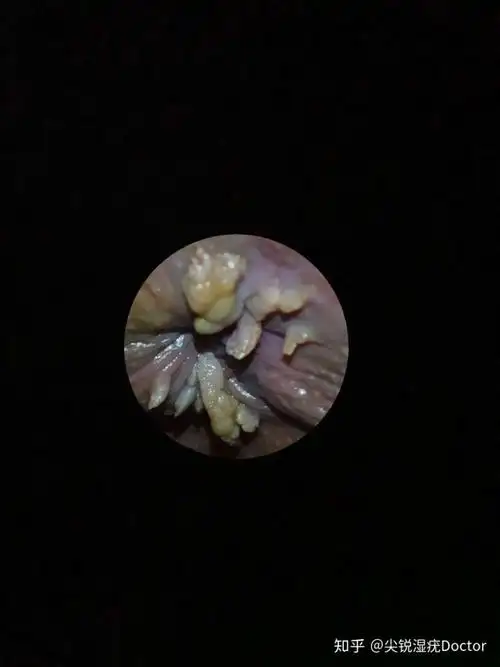

上图是尖锐湿疣的图片,它的发病区域主要是在私处,而且发病区域的形状